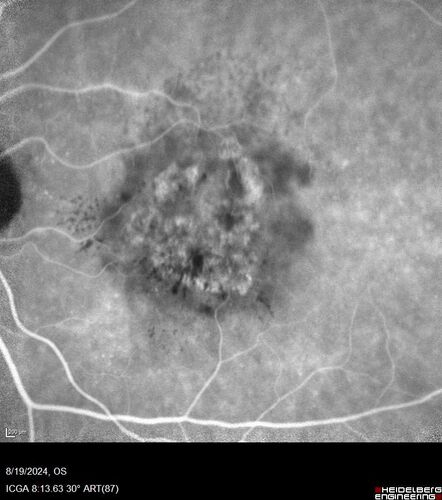

Wet AMD - Occult CNVM and Geographic atrophy

77 year old female with mild vision loss - 20/32 - responded to Avastin

Occult CNVM wet AMD and Geographic Atrophy